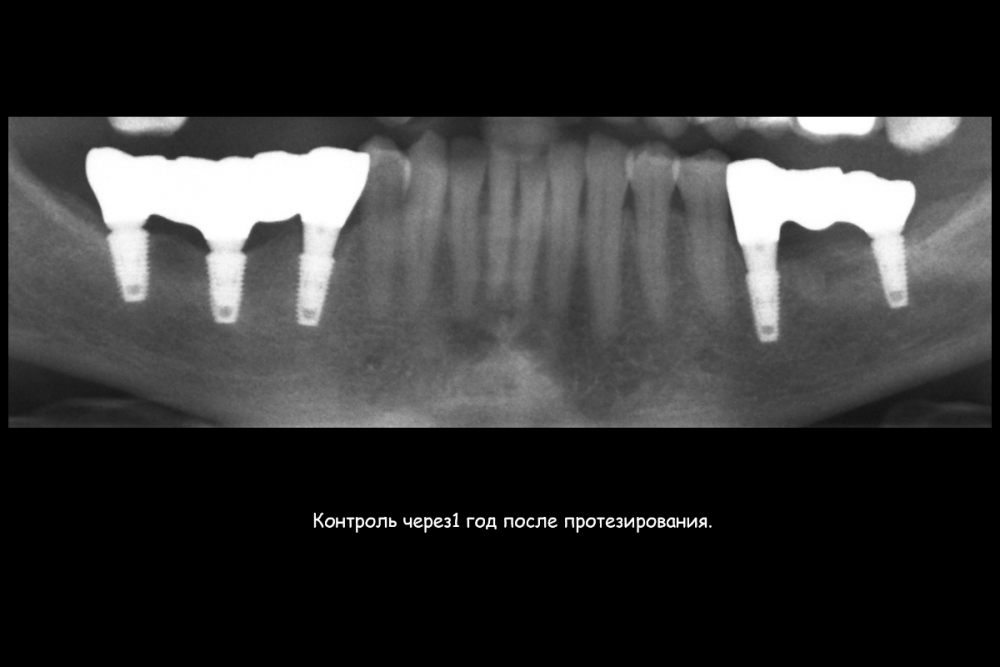

Карен Аванесов Опубликовано 23 июля, 2021 Поделиться Опубликовано 23 июля, 2021 (изменено) Этот пациент особо радует гигиеной на осмотрах, всегда очень чисто, приятно это. Важно когда пациент ответственный. По кейсу все на сгустке крови, без "проленового" рта. Изменено 23 июля, 2021 пользователем Карен Аванесов 6 3 1 Ссылка на комментарий